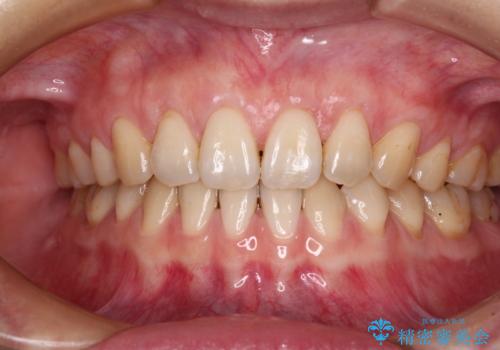

- 他院で矯正治療を終えた結果、上顎前歯の歯肉が退縮してしまい、根が見えていることが気になるとのことで来院された患者様です。

歯肉退縮に対して、上顎からの結合組織移植術(CTG)により、歯根の被覆を行うとともに、歯肉の厚みを増すことで将来の退縮リスクを抑制することとしました。

必要な被覆量が多かったため、満足のいく被覆を達成するには2度の手術が必要と思われましたが、生着がよく、術後の注意事項を徹底したことで、十分な被覆量を達成することができました。